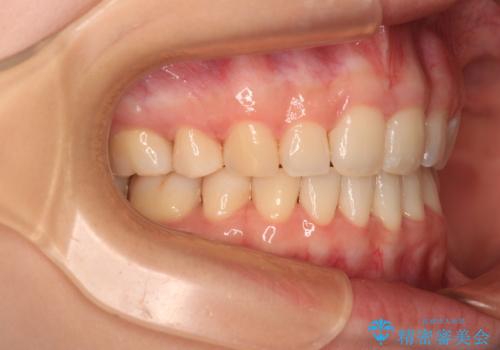

口元の突出感のない、すっきりとした仕上がりとなりました。